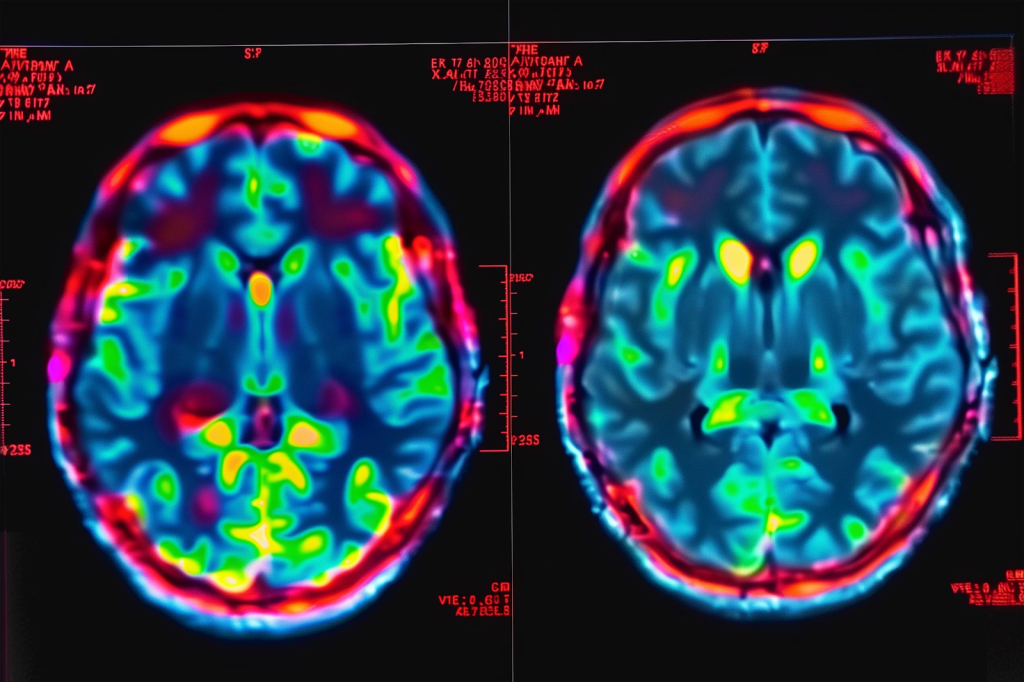

How SPECT Differs from Other Brain Imaging Techniques

Functional brain imaging like SPECT is different from MRI or CT scans. Those show the brain’s structure. SPECT shows how the brain functions.

SPECT and PET (Positron Emission Tomography) scans are both about brain function. But SPECT uses a different tracer and method. It’s more common and cheaper than PET, making it easier for patients to get.

SPECT vs. PET Scans

SPECT and PET scans are both used to see how the brain works. They use radioactive tracers but differ in how they work. PET scans are more sensitive and have better images than SPECT. But SPECT is cheaper and easier to get, making it good for some tests.